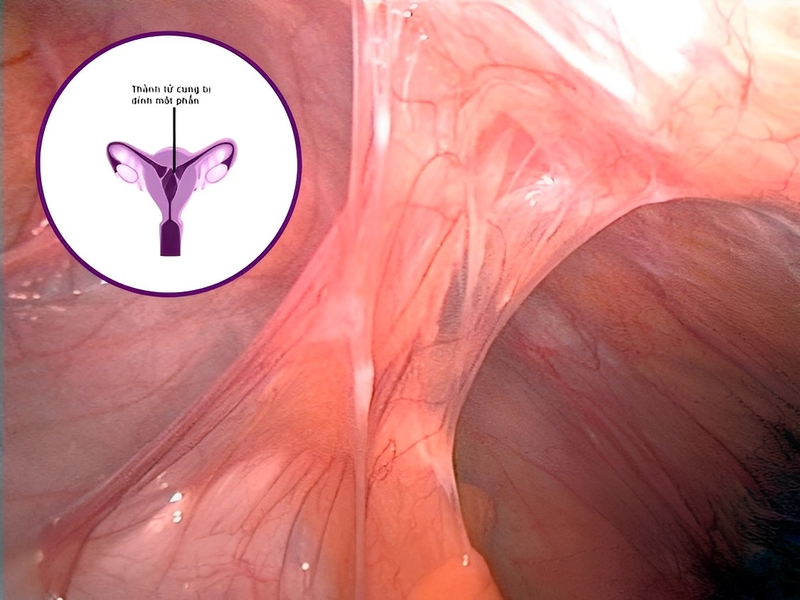

Buồng tử cung có 2 thành gồm thành phía trước và thành phía sau giống như một quả bóng bay. Khi hai thành này bị dính lại với nhau sẽ gây ra tình trạng dính buồng tử cung. Điều này cản trở quá trình tái tạo nội mạc tử cung và chắc chắn nó sẽ ảnh hưởng đến quá trình thụ thai.

Nếu thành trước và thành sau của buồng tử cung dính hoàn toàn, tinh trùng sẽ không thể gặp trứng để thụ thai. Nếu thành trước và thánh sau của buồng tử cung dính một phần, trứng và tinh trùng vẫn có thể gặp nhau nhưng trứng đã thụ tinh không thể vào làm tổ trong tử cung. Điều này dẫn đến nguy cơ sảy thai hoặc mang thai ngoài tử cung. Dính thành tử cung là một trong những nguyên nhân gây vô sinh thứ phát. Đây là lý do nhiều bệnh nhân muốn biết cách điều trị dính buồng tử cung hiệu quả.

Phương pháp điều trị dính buồng tử cung bằng nội soi không cần mổ vùng bụng cũng không phải xẻ tử cung. Điều này khiến người bệnh yên tâm hơn khi điều trị. Với cách điều trị dính buồng tử cung này, bác sĩ sẽ dùng dụng cụ nội soi có gắn thiết bị chiếu sáng và camera. Qua hình ảnh thu được có thể xem từ màn hình, bác sĩ sẽ tiến hành tách dính và đặt dụng cụ ngăn cách hai lớp thành của buồng tử cung để phòng ngừa tái dính.